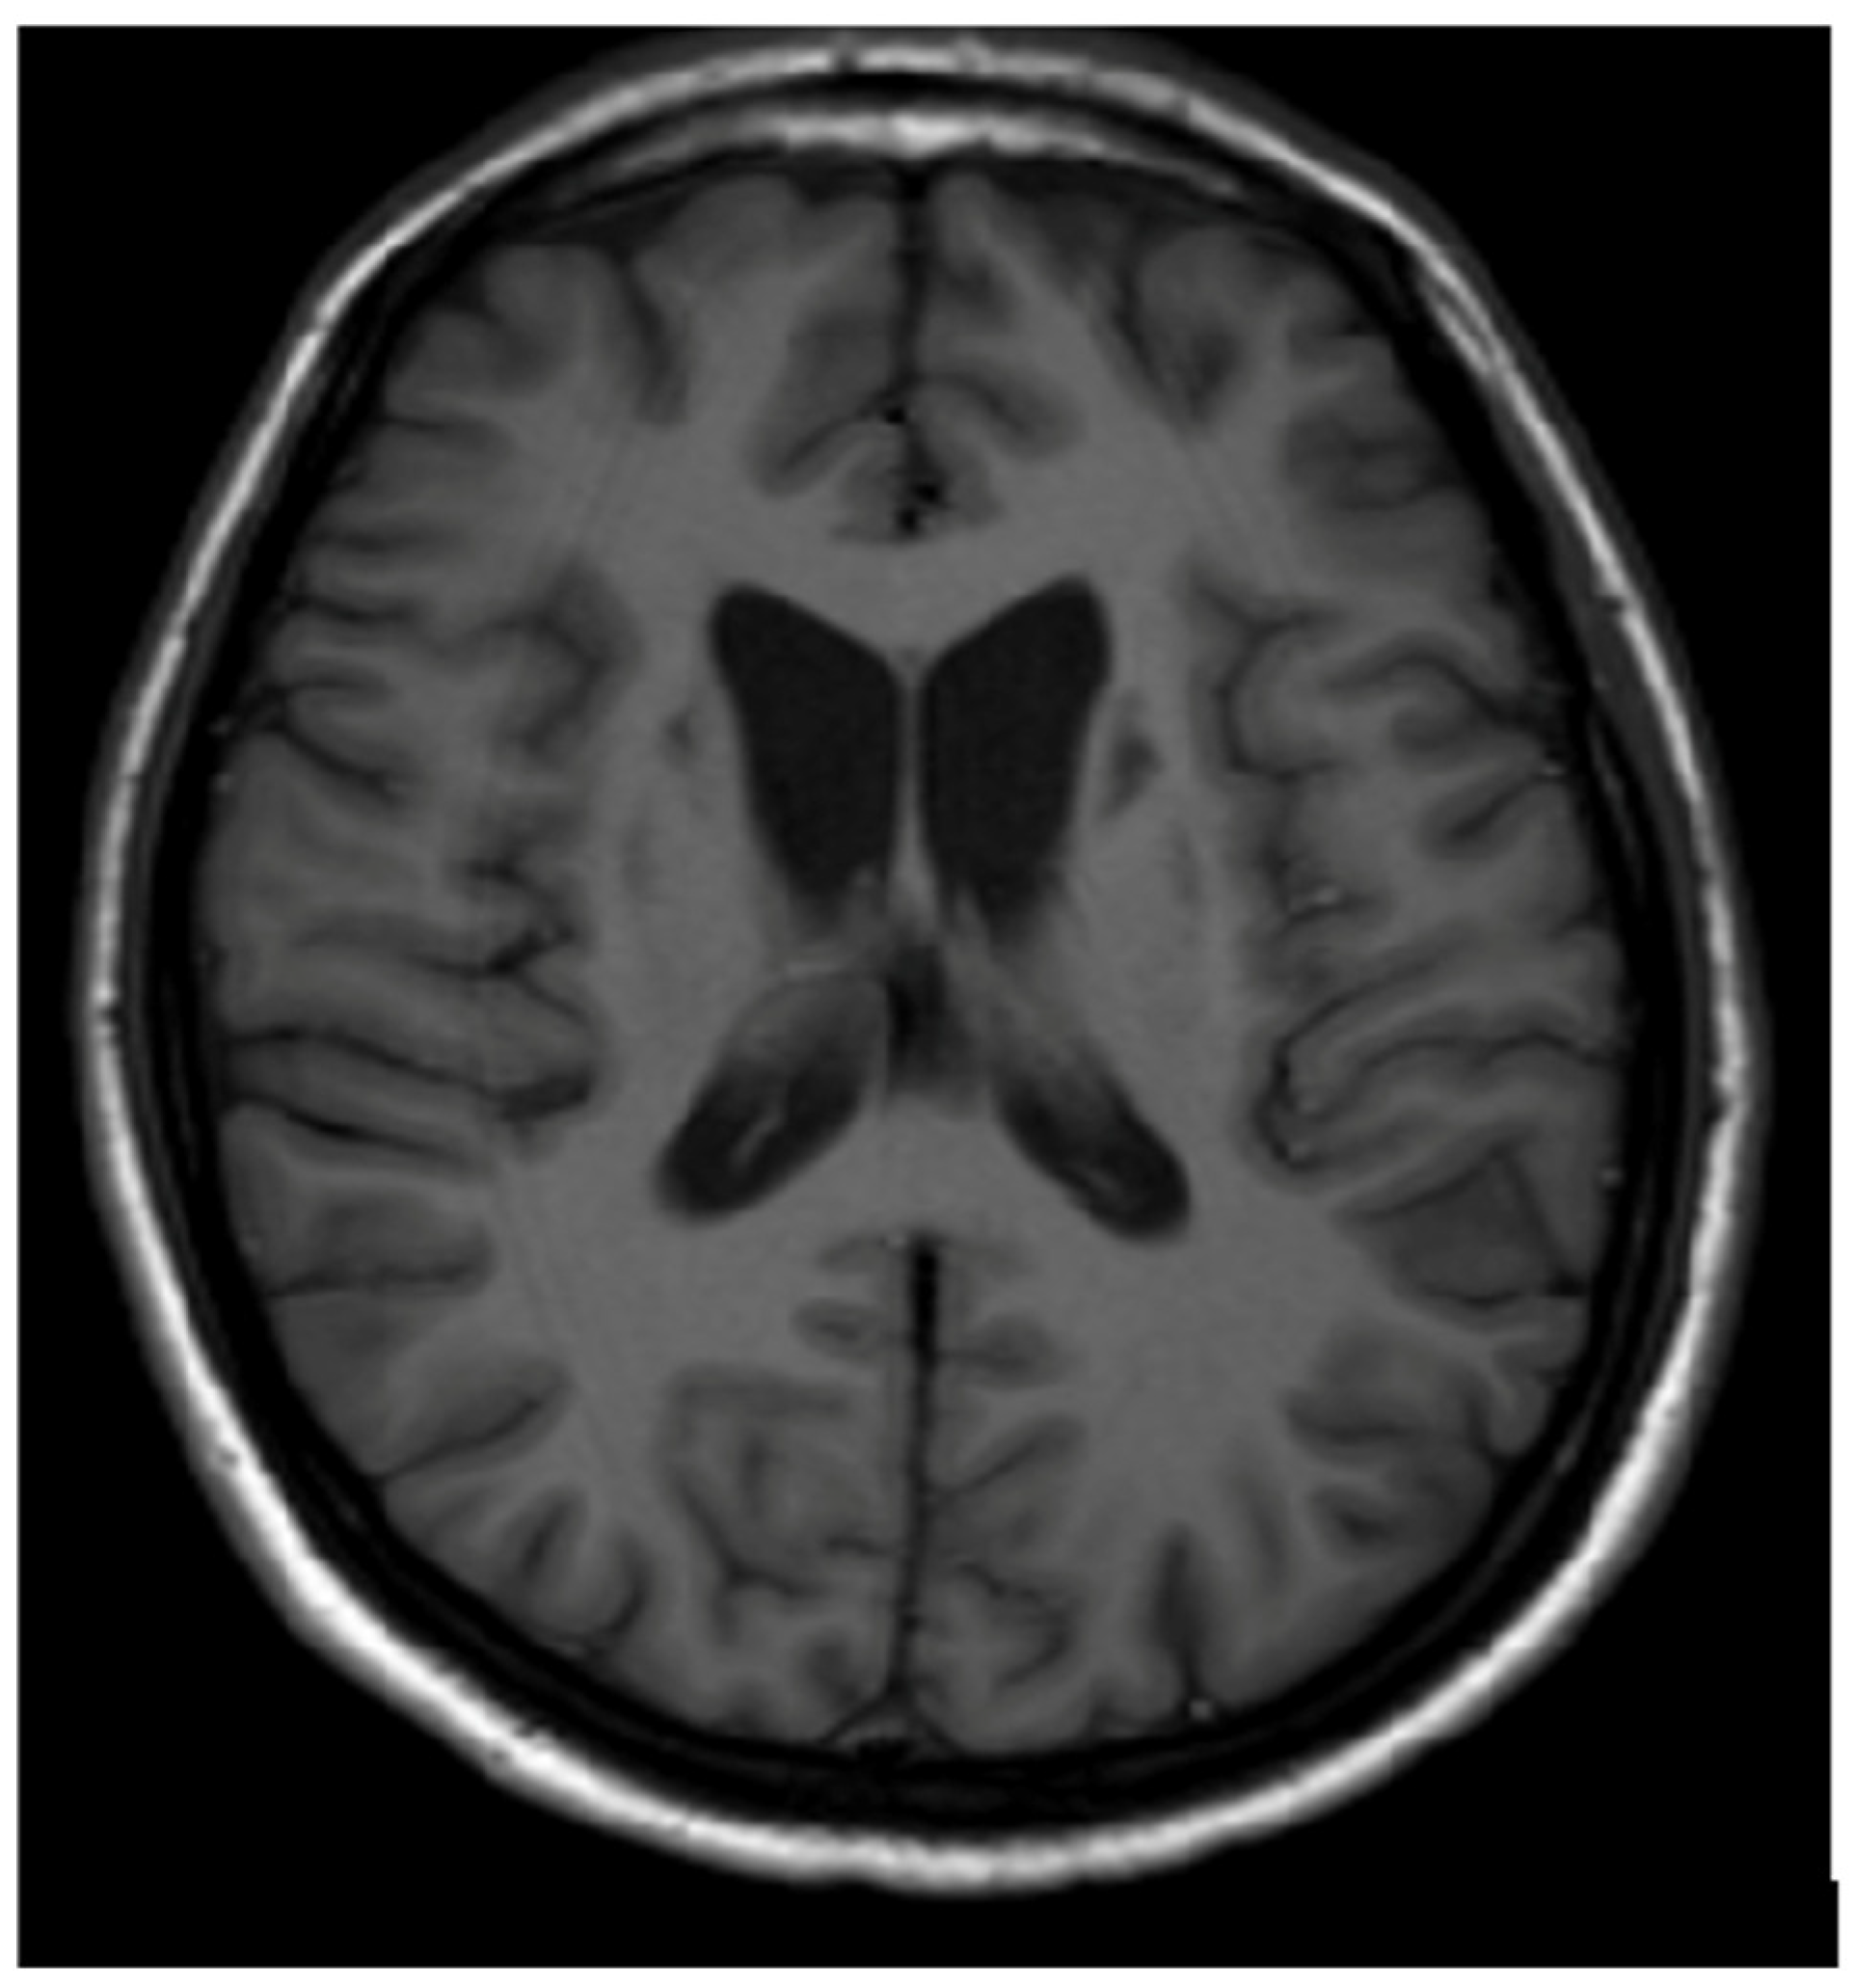

3.1. Classical Brain MRI Examination in WD Patients

5. Neuroradiological Pathognomonic Signs of WD